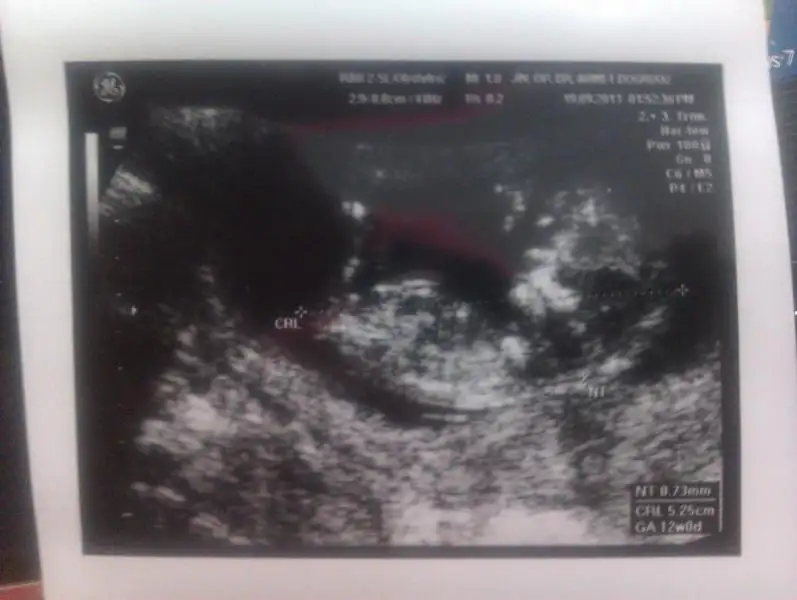

merhaba arkadaşlar elımde son ultrasyon görüntüsü yok ama bu resım var burdan anlaşılır mı? anlaşılırsa size zahmet bı yorum yapın teyzeleriiMerakla cevaplarınızı beklıyorummm

Resim çok kucuk yanılma payıyla birlikte ben erkek diyorum Hayırlısı olsun.

Canım bebegın yan yatmış sanki o yüzden yorum yapamadım. ama bir çıkıntı gibi birsey var ayak kemiği fln değilse epey inceledim erkek diyorum canım (görünen çıkıntı nubsa tabi) Gönlündeki olsun canım.

Cnm bana da erkek gibi geldi.sanki benimkine benzeyen beyaz renkte o cikintiyi goruyorum.benimkine dr.erkek dedi ona dayanarak seninki de erkek bence.

Bana kiz gibi geldi.nub belirgin sekilde paralel diyorum ben.